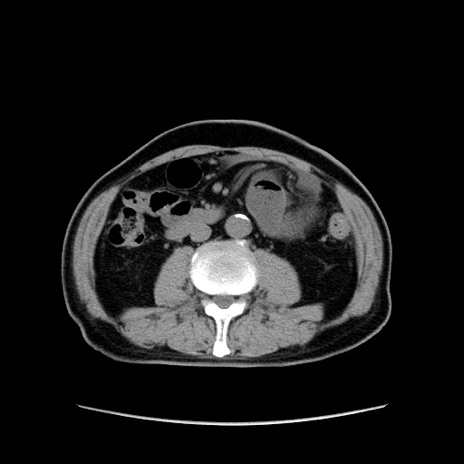

症例24(横断像)

【症例】80歳代男性

【主訴】左側腹部痛、嘔吐

【現病歴】本日早朝より左腹部に痛みあり。昼頃嘔吐認めたため、救急要請。

【既往歴】直腸癌(Mile手術)、胆摘

【身体所見】意識清明、BT 35.9℃、BP 221/93mmHg、SpO2 97%(RA) 、腹部:左ストーマ周囲に限局性の腹部膨隆あり。 膨隆部自発痛・圧痛あり・軟。

【データ】WBC 7700、CRP 0.09